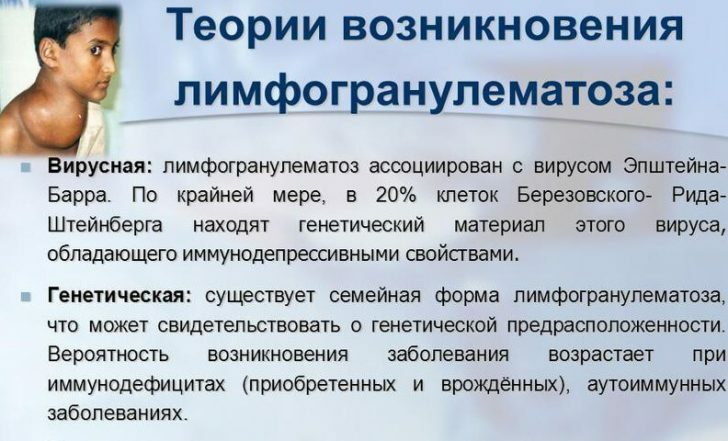

Раздел: Образы вокруг